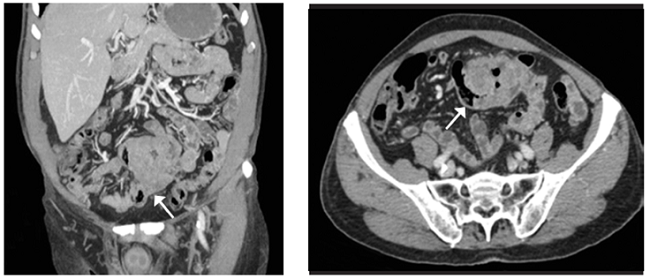

Paciente masculino de 73 años, con antecedente de amputación del primer dedo de mano por melanoma amelanótico Clark IV / Breslow 9 mm y linfadenectomía cervical, en seguimiento por Oncología, sin detectar recidiva. Cuatro años después, acude a urgencias presentando dolor abdominal y vómitos de un mes de evolución. En la tomografía computarizada (TC) abdominal se destaca un conglomerado de asas intestinales sin establecer causa (Figura 1).